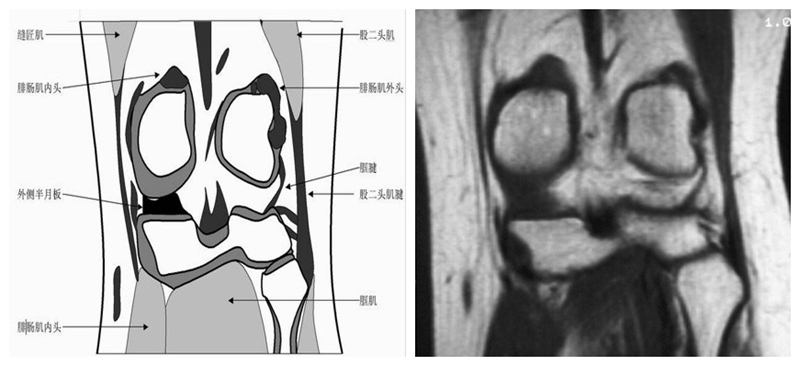

膝关节冠状面MRI解剖

显示内外侧副韧带、腘肌和拱状韧带,有无信号和结构改变,侧重关节胫股软骨的两边和半月板的体部。

冠状位解剖第一层